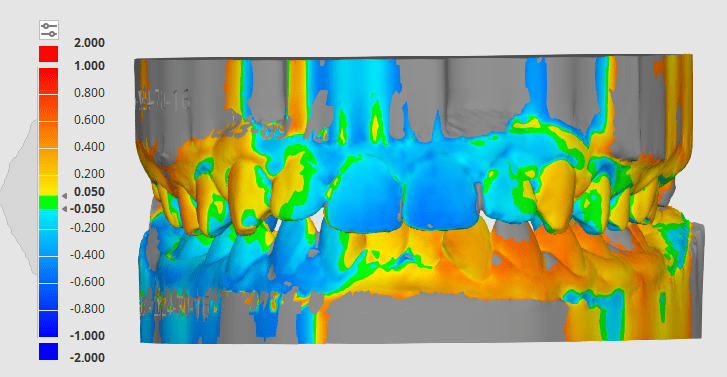

Adaptive Orthodontics Pre-Op Analysis – 2020-11-25 Age : 9 Class 2 div I and div IIMixed DentitionLower lip entrapment NORMALLY LOWER LIP ENTRAPPED BEHIND UPPER ANTERIOR NORMALLY LOWER LIP ENTRAPPED BEHIND UPPER ANTERIOR PROCLINE (OVERJET) UPPER ANTERIORDIASTEMA (SPACING) – TONGUE THRUSTLOWER LIP ENTRAPMENTNARROW (GOTHIC) ARCHDEEP BITE – SOFT TISSUE TRAUMA STAGE 1 RETRACT UPPER ANTERIORS… Read.

Ella C. – RME + Myobrace – Mixed Dentition, Class II Div 1 with Moderate to Severe Crowding